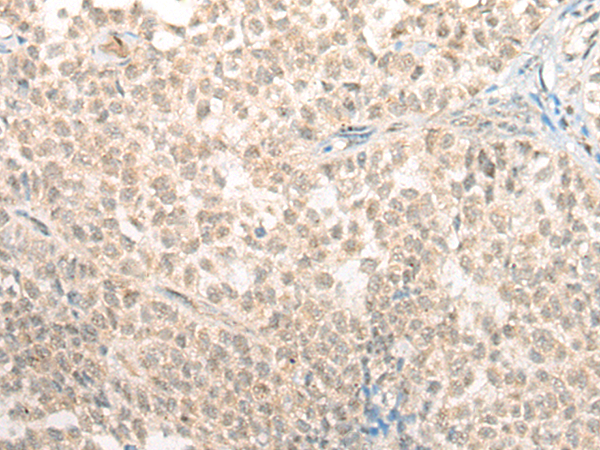

分类: 科研抗体货号: P13189别名: GAIP; RGSGAIP应用: IHC反应种属: Human, Mouse, Rat